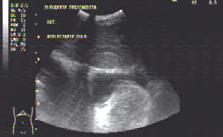

Fig.5. Secțiune subxifoidiană. Cord drept dilatat

Fig.6. Secțiune intercostală dreaptă. Colecție pleurală masivă. Atelectazie pulmonară de compresiune

Fig.7. Secțiune intercostal drept. Colecție Spațiul Morrison

Fig.8. Secțiune longitudinală suprapubiană Colecție recto-vezicală

• se apreciază de asemenea plămânul, cavitatea pleurală (fig.6) și peritoneală (fig.7, 8) care pot compromite volumul vascular prin anumite patologii acute de tip „pierdere de fluide – loss of fluid from the tank”; prezența colecției pleurale asociată cu colapsul parenchimului pulmonar și reducerea bronhogramei aerice indicând necesitatea drenajului pleural; prezența colecțiilor peritoneale necesită evaluarea prin puncție ecoghidată a aspectului pentru decizie terapeutică, indicație chirurgicală sau trimiterea spre o investigație imagistică de tip computer tomograf; o conținutul intravascular („PIPES“)